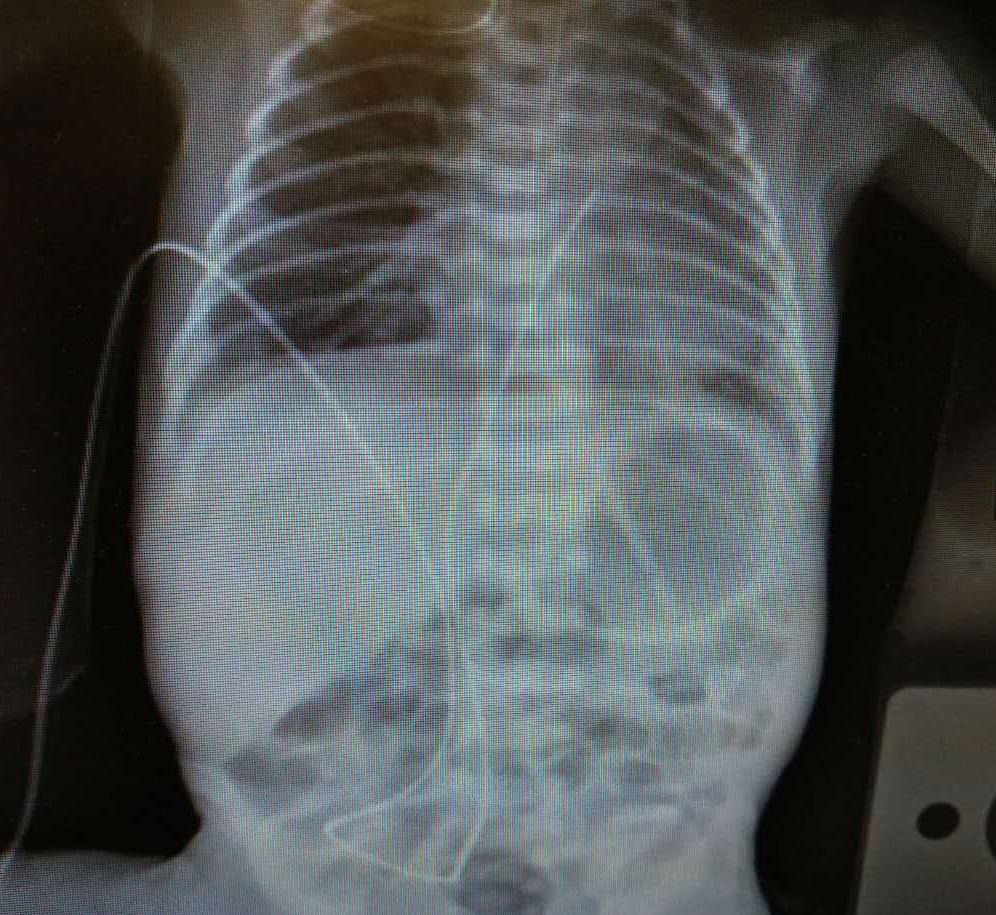

我院新生儿科成功开展早产儿脐动静脉置管术

图片尺寸1280x960